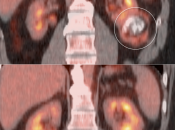

RCCA: An Easily Overlooked Primary with PET/CT (3 Big Limitations)

- FDG is excreted and accumulates in the kidney, easily masking areas of pathologic uptake.

- Many renal cell carcinomas are only mildly FDG-avid.

- Nearly every PET/CT scan is performed without intravenous contrast, markedly limiting evaluation of the kidneys on the CT portion of the exam.

- These 3 limitations lead to a sensitivity of only ≈ 60% for the detection of a primary RCCA lesion.

Primary Lesion: Because many primary RCCA lesions are only mildly FDG avid, we must raise a suspicion of RCCA for any FDG-avid renal lesion (cystic or solid) — unless we can clearly characterize it as a fat-containing angiomyelolipoma.

Metastatic Disease: Metastatic RCCA lesions are usually more FDG avid than the primary lesion (nearly all demonstrate metabolic activity greater than liver uptake).